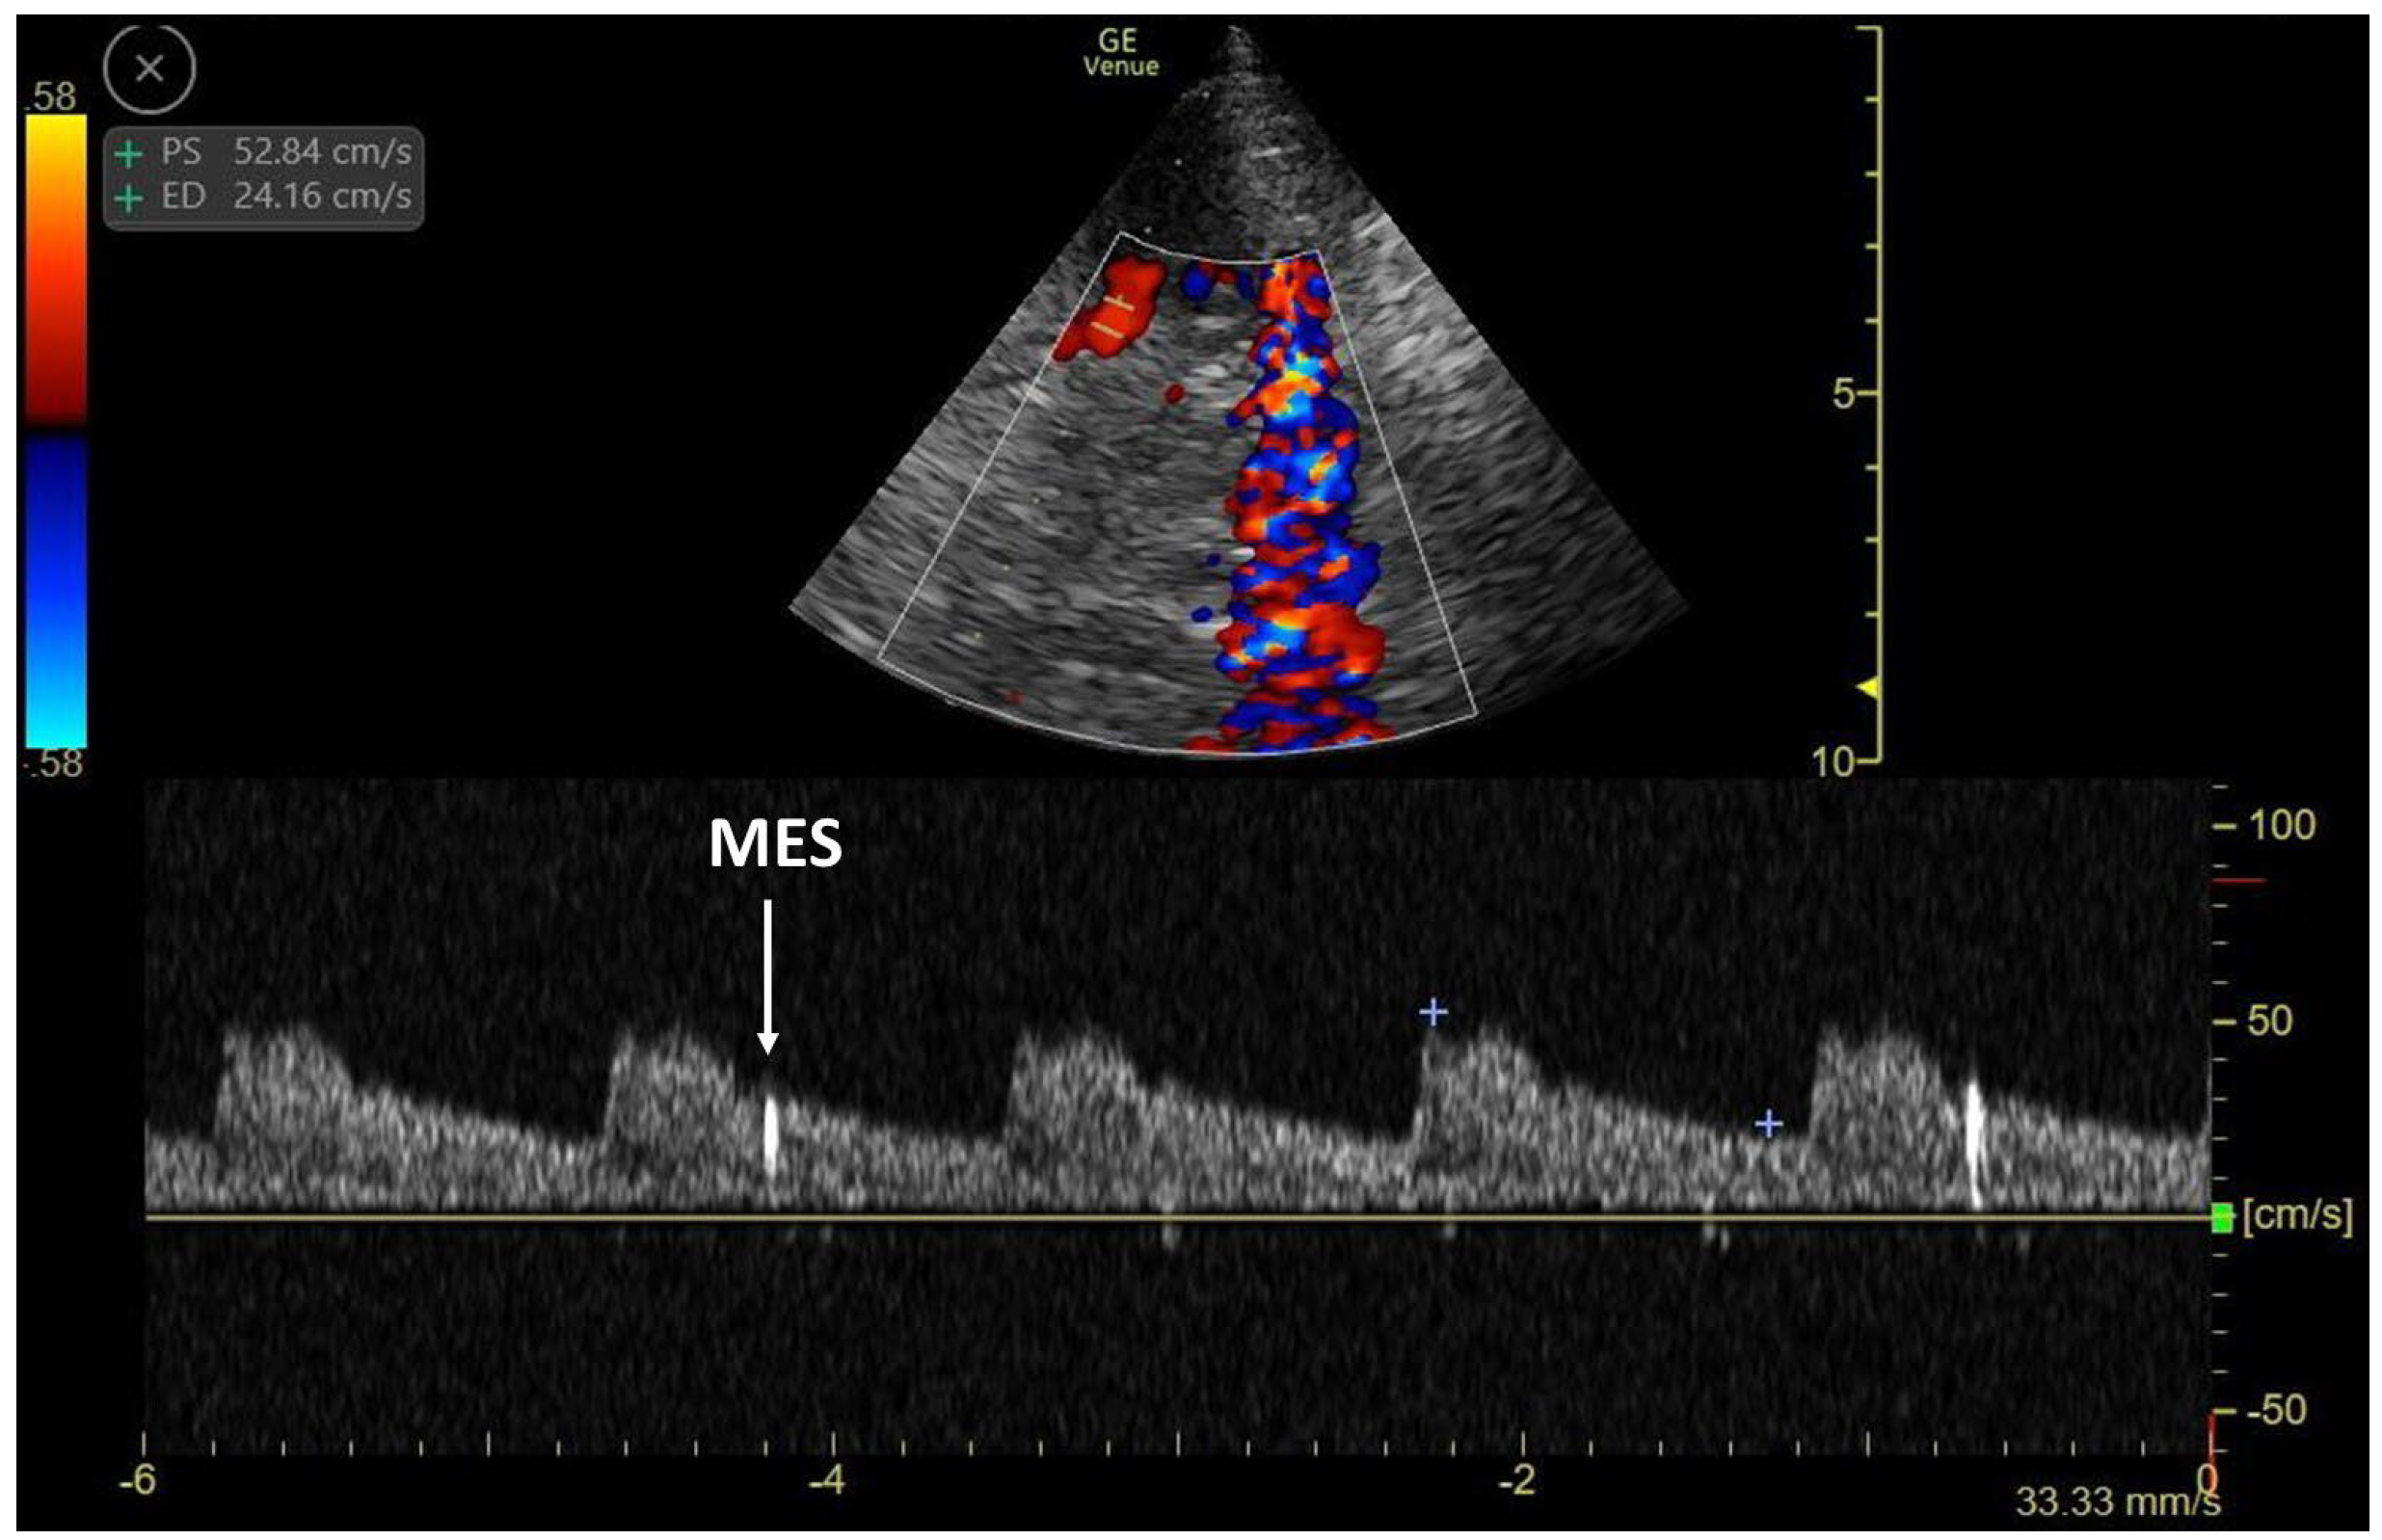

3.3. TCCD MES-Positive Case 3

| MES | microembolic signals |

| TCCD | Transcranial–ecocolor Doppler |

| TEE | transesophageal echocardiography |